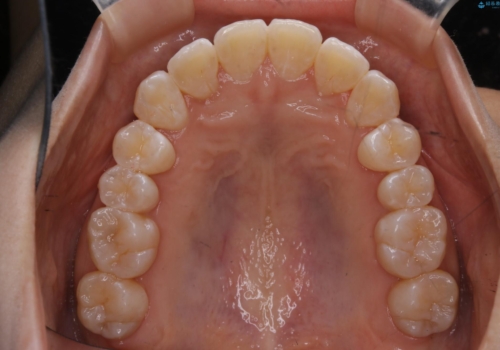

前歯のがたつきとオープンバイト:インビザラインでまとめて治す

- 噛み合わせと、前歯のがたつきが気になるとご相談にいらした方です。インビザラインFULLで綺麗な歯並びと噛み合わせを作ることが出来ました。

オープンバイトの方への治療は、通常抜歯を行いワイヤーによる矯正治療を行うことが多いですが、今回はインビザラインの特性を生かし、非抜歯にて綺麗な歯並びを作ることが出来ました。